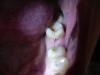

Алекс10 Опубликовано 5 ноября, 2010 Поделиться Опубликовано 5 ноября, 2010 (изменено) Добрый день! Решила обратиться к Вам, т.к. по поиску не нашла подобного случая. Четыре месяца назад из-за сильной боли в нижнем 6-ом слева зуб был удален (терапевт и хирург сошлись во мнении, что лечение не целесообразно). Была киста, удалена удачно (не вытекла) с зубом. Через месяц обратилась к терапевту за лечением, т.к. в нижней 7-ке слева со стороны свежеудаленного зуба открылся кариес (сбоку в зубе дырка была глубокая и черная). Этот зуб ранее был пломбирован (само дупло). Врачу сообщила, что после удаления 6-ки этот зуб периодически реагирует на высокую и низкую температуру. Без рентгеновского снимка зуб был запломбирован. Остальные зубы со слов врача в лечении не нуждались. После проведенного лечения не ем на левой стороне. Боли при попадании жидкости любой температуры (и теплой и прохладной, любой), но уже одновременно на левых нижних 4, 5 и 7 (5-ка ранее была пломбирована, но не беспокоила). В остальное время зубы не беспокоят. Т.е. пока не удалили 6-ку вообще никакой реакции на воду небыло. Помогите, пожалуйста, разобраться. Снимки старалась сделать как можно отчетливей, надеюсь, что они разборчивые. Заранее благодарю. Здесь расположен рентген-снимок: http://s010.radikal.ru/i311/1011/f2/9df9bb126eea.jpg Изменено 5 ноября, 2010 пользователем Алекс10 Ссылка на комментарий